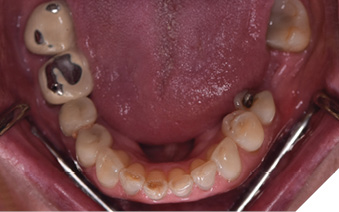

A 65-year-old woman comes to the office with the chief complaint of worn-down teeth, missing teeth, tooth sensitivity, especially on maxillary teeth and TMJ pain. Her past medical history was reviewed and was significant for asthma, insomnia, hypercholesterolemia, hypothyroidism, and anxiety disorder. She denied any sleep disturbances. Her medications included salbutamol, ezetimibe, quetiapine, and levothyroxine. She referred to being allergic to dust and shellfish and sensitive to propofol. She had a right mastectomy in 2014 due to breast cancer. No chemotherapy or radiation was done. Her diet was considered normal, and she denied any consumption of acidic drinks and denied any history of regurgitation. She denied any parafunctional habits during the day. She was using a maxillary transitional partial denture since she had lost some of her teeth due to fracture and caries. No other problems were evidenced. Intraoral exam showed moderate attrition lesions of posterior teeth, porcelain fused to metal crowns on teeth 46 and 47 had the porcelain portion worn down, exposing the metal substructure. Missing teeth included teeth 14,15,16,18,24,28, 36,38,48. Palatal surfaces of maxillary anterior teeth also appeared worn down. An abfraction lesion was found on tooth 23. No carious lesions were found in any of her teeth. Composite restorations on mandibular anterior teeth were chipped or were missing (Figs. 6-11) She also presented with limited mouth opening: 35 mm interincisal distance at maximum opening. There was bilateral pain on palpation of preauricular areas. Her pain was the worst early in the morning which suggested night parafunction. No crepitus, or joint clicking were found.

Fig. 6

Fig. 7

Fig. 8

Fig. 9

Fig. 10

Fig. 11